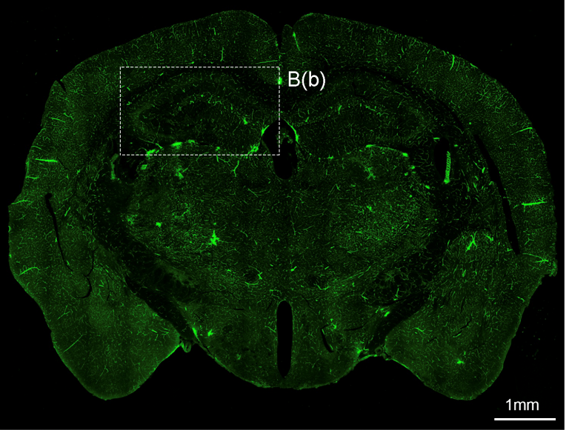

신경면역학 실험실(이찬희 교수님)

biomedical_JW_MS_K2WT001_S